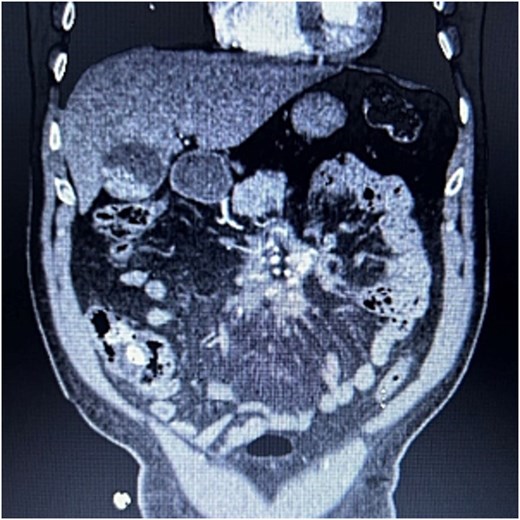

A 76-year-old male who presented to the outpatient clinic for evaluation of a central mesenteric mass. Patient reported a several year history of vague abdominal pain which progressively worsened over the few months prior to presentation. He denied any history of abdominal trauma or associated symptoms such as weight loss, flushing, or diarrhea. 24-h urine studies and serum serotonin levels were unremarkable. CTA of the abdomen and pelvis showed a 2.5 × 1.5 × 2.7 cm calcified mesenteric mass in the mesenteric root with tethering to the surrounding the mesenteric vessels and no evidence of bowel obstruction (Fig. 4). Upper and lower endoscopy were performed and were unremarkable. A Ga-DOTATATE PET can showed an infiltrating soft tissue density with calcification in the mesenteric root measuring 2.4 × 4.4 cm, but without prominent uptake (maximum SUV of 2). No other lesions were noted. Patient subsequently underwent elective exploratory laparotomy with incisional biopsy of central mesenteric mass. Intraoperatively, an infiltrative, calcified soft tissue mass within the central mesentery with encasement and tethering of the superior mesenteric artery was found. There was no evidence of bowel perforation or obstruction. Preliminary pathology was consistent with sclerosing mesenteritis. Specimen was sent for further analysis at Cleveland Clinic’s Robert J. Tomsich Pathology and Laboratory Medicine Institute (RT-PLMI). Further analysis did not show evidence of neoplasm and all neuroendocrine markers were negative, confirming the diagnosis of sclerosing mesenteritis. Patient continued to report vague abdominal discomfort post-operatively and was referred to rheumatology for consideration of anti-inflammatory therapy and tamoxifen.

CTA abdomen/pelvis showing central calcified mesenteric mass, Case 2.